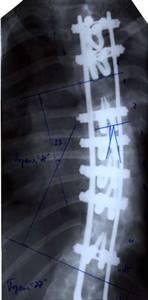

| Результат коррекции сколиотической деформации эндокорректором с деротационными скобами |

| Больной П-ко, 15 лет Поясничный сколиоз III степени |

Результат оперативного лечения |

|

| Больная Л-ч, 12 лет сколиоз IV степени |